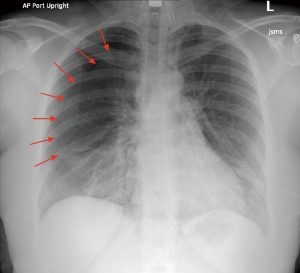

Despite the non-identification of a pneumothorax in the operating room on fluoroscopy (Figure 3), the patient was noted to have a right-sided pneumothorax of approximately 4 cm (about 1.57 inches) on a subsequent upright chest radiograph in the recovery room (Figure 4). The patient did not have decompensation of vital signs, with her lowest oxygen saturation being 94%. The patient did not have major sequelae of this other than to require a pigtail chest tube placed by interventional radiology under the recommendation of a cardiothoracic surgeon consultation (Figure 5). The patient responded well and discontinued the chest tube within 24 hours. The chest tube was removed by the interventional radiologist once they were determined to be stable upon inspection with additional CXRs (Figure 6).

Figure 4 Post-operative upright radiograph demonstrating right pneumothorax. Arrows indicate the borders of the lung where collapsed. AP, anterior-posterior.